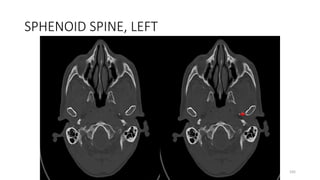

SPHENOID SPINE, LEFT

Sphenoid, greater wing

Sphenoid spine